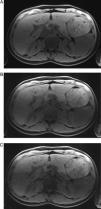

ResultadosLa adquisición en apnea proporcionó mejor calidad de imagen y menos artefactos que la adquisición con respiración libre. La tasa de artefactos fue mayor para FR más altos. La mejor calidad se obtuvo con secuencias en apnea con un FR=2. Un FR=4 presentó tasas menores pero diagnósticas (p=0,004). La severidad de los artefactos, en especial el granulado de los píxeles (p=0,004), hizo que las secuencias con un FR=6 no fueran diagnósticas. Ninguna de las secuencias obtenidas con respiración libre fue diagnóstica.

ResultsImage quality and extent of artifacts were better with breath hold than with free breathing acquisitions. The rate of artifacts increased with higher RF. The best quality was acquired with breath hold sequence using RF=2. RF=4 had lower but diagnostic rates (P=.004). The severity of artifacts, mainly pixel graininess (P=.004), rendered sequences with RF=6 non-diagnostic. All sequences were non-diagnostic in free breathing acquisitions.